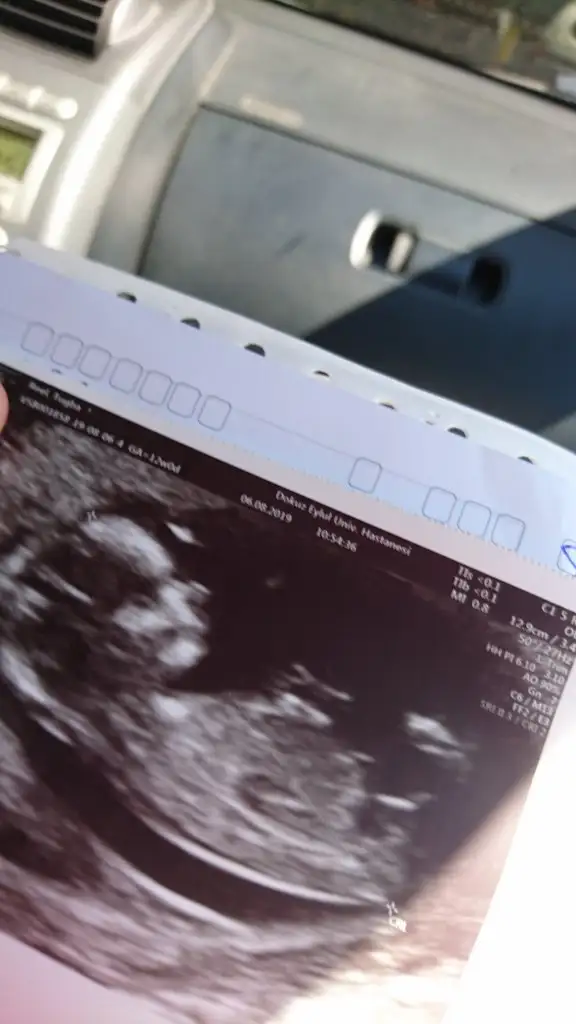

Kızlar benim kuzuya da bi yorum yapabilirmisiniz lütfen

Bide bunlar var bu arada zaman ayırıp yorum yaptığınız için teşekkürler

şu 3. usg deki şeyin ne olduğunu merak ediyorum hala.. ayakları havaya dikip popoyu bize çevirdi poz verdi..

o görüntü geçen hafta videoda bariz ortada çıkıntı şeklinde idi -ki usg foto da bile çıktı anlamadım..

o yüzden kafam karıştı..

bu hafta ki görüntülemede önden (yani bebeğin karın kısmından bacak arası bakışı) baktı 10-15 sn arada bi çıkıntı gibi gbişi vardı ama henüz erken dedi..

bakalım kısmet hayırlısı ne ,1 ay sonra netleşecek..